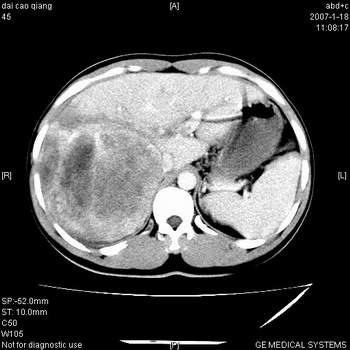

符合巨块型肝癌表现:

1、平扫低密度,增强后表现为快进快出。

2、动脉期可见迂曲的动脉供血血管

3、并可见门静脉右支癌栓形成

4、可见假包膜

5、腹主动脉旁结节影,考虑肿大淋巴结。

肝右叶巨大不均匀低密度肿块,前缘有假包膜,增强明显的呈快进快出表现,门脉右支有癌栓,病人虽然年轻但还是首先考虑肝右叶巨块形肝癌,病人血象高只能说有合并感染。不支持肝脓肿。